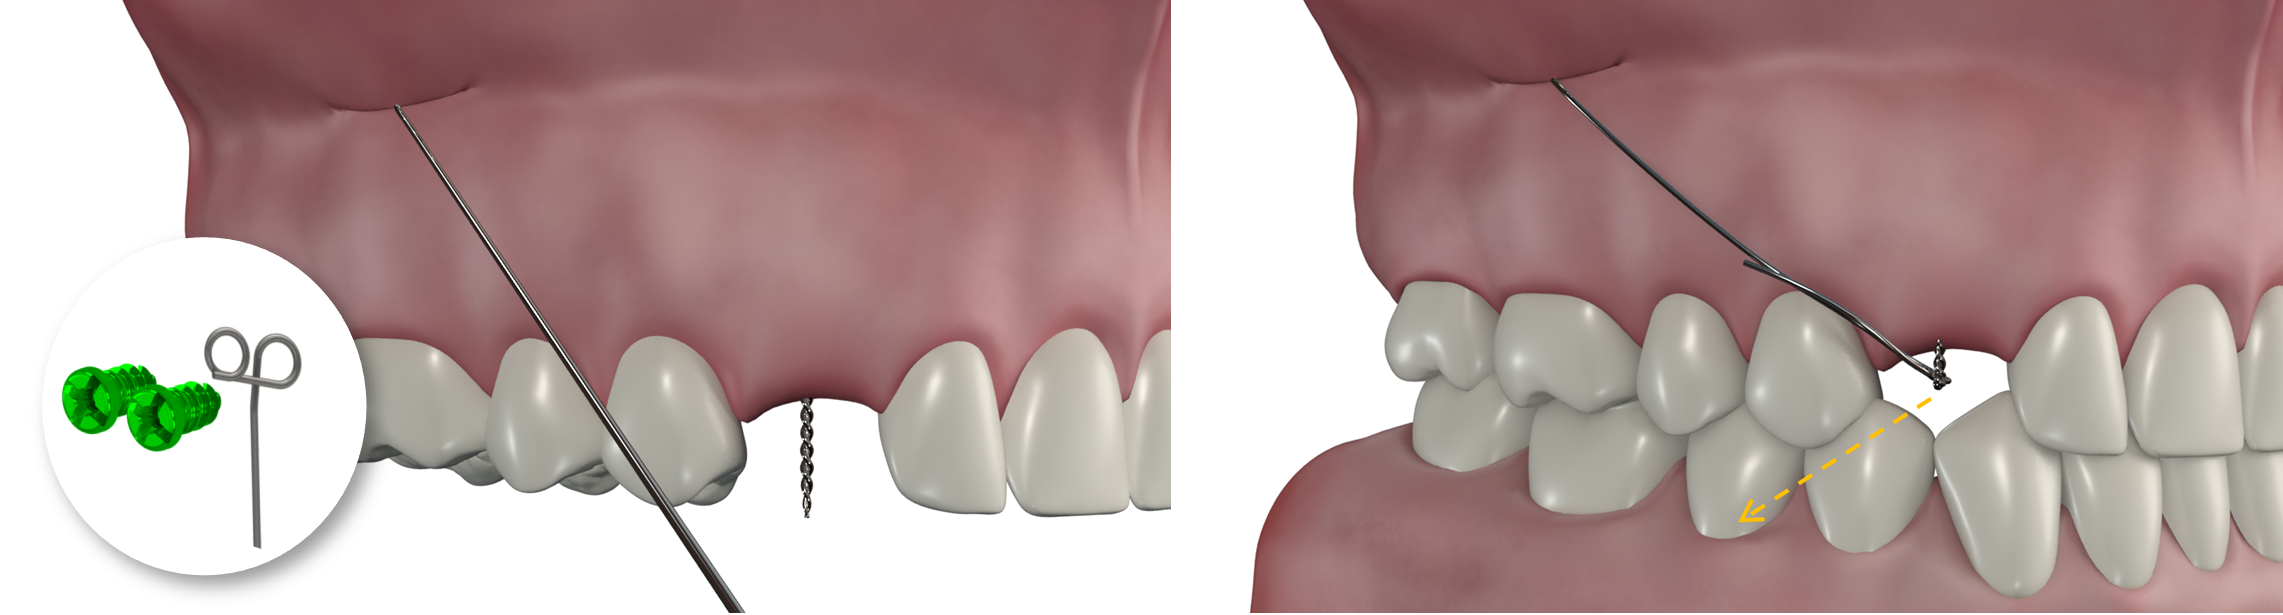

Site d'implantation

Kit Traction de canine incluse (2 vis + 1 CT8-1 droit ou gauche)

NB : respecter le côté droit / gauche

Processus zygomatique

Mécanique

Le dégagement chirurgical de la couronne de la canine incluse vient d’être réalisé, la ligature accrochée au bouton collé à sa surface émerge à son emplacement naturel d’éruption.

Le lambeau d’accès à la canine a été refermé et suturé.

Le bras du CT8 est activé vers le bas pour une canine vestibulaire, vers l’extérieur pour une canine palatine. Il est replié sur lui-même et accroché à la ligature reliée à la canine au niveau de son espace naturel d’éruption.